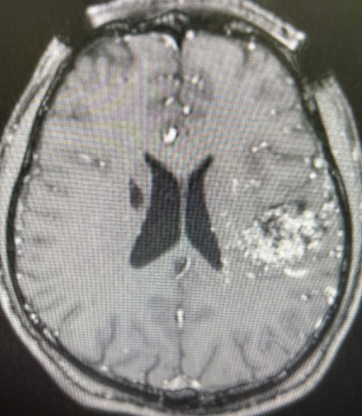

Case 2, female patient, 56 years old, complained of left limb weakness and difficulty walking for 2 weeks. Diagnosis: Multiple brain metastases from lung cancer. Figure A-D

Figure A: 2022-25 Gamma knife treatment localization, right frontal tumor with severe edema around the lesion.

Figure B: Simultaneous gamma knife treatment of left temporal tumor from 2022 to 02-25

Figure C: July 25th, 2022. After 5 months of surgery, magnetic resonance imaging showed that the right frontal tumor disappeared and the patient walked freely.

Figure D: 2022-07-25, magnetic resonance imaging reexamination, left temporal tumor also disappeared.